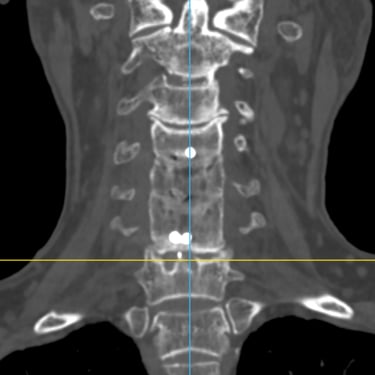

🧠 Cirugía de Revisión Cervical: Estabilidad Posterior en Seudoartrosis y Enfermedad del Segmento Adyacente.

La seudoartrosis cervical con subsidencia del cage y enfermedad del segmento adyacente genera dolor e inestabilidad. La artrodesis cervical posterior con tornillos a masas laterales y pediculares es una técnica eficaz para lograr una fijación sólida, mejorar la estabilidad y aliviar los síntomas neurológicos.